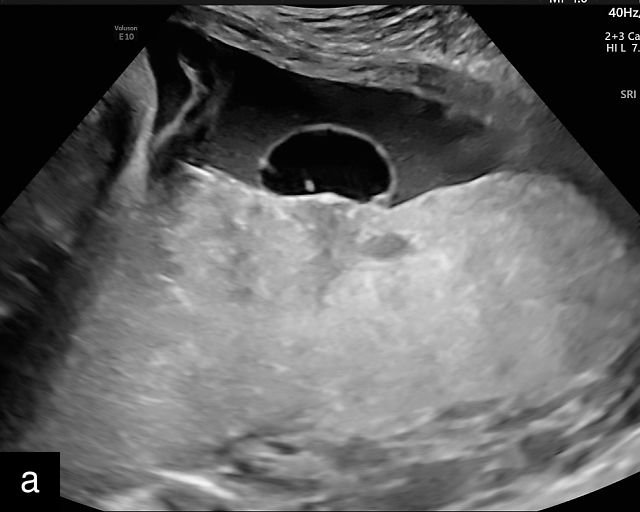

In the early first trimester, trophoblastic tissue appears as an echogenic ring encircling the gestational sac (Figure 1a). By the late first trimester, the placenta becomes recognizable as a distinct structure on ultrasound (Figure 1b). Initially, it presents as a homogeneous echogenic mass (Figure 1b–d) but undergoes progressive differentiation, becoming more heterogeneous as pregnancy advances from the second to third trimester (Figure 1e–g). By the third trimester, cotyledons become discernible, and in the late third trimester, calcifications frequently appear basally and around the cotyledons (Figure 1g).

1

Ultrasound images of development of the placenta (P/p). (a) Trophoblastic tissue appearing as an echogenic ring surrounding the gestational sac at 6 weeks' gestation. (b) Placenta at 12 weeks has become a discrete, uniformly echogenic mass. (c) Placenta at 17 weeks. (d) Placenta at 20 weeks. (e) Placenta at 27 weeks. (f) Placenta at 33 weeks. Increasingly, differentiation and heterogeneous appearance is seen, with demarcation of the cotyledons. Basal calcifications are beginning to appear. (g) Placenta at 40 weeks, showing a distinctly heterogeneous appearance, with clear demarcation of the cotyledons and presence of calcifications.